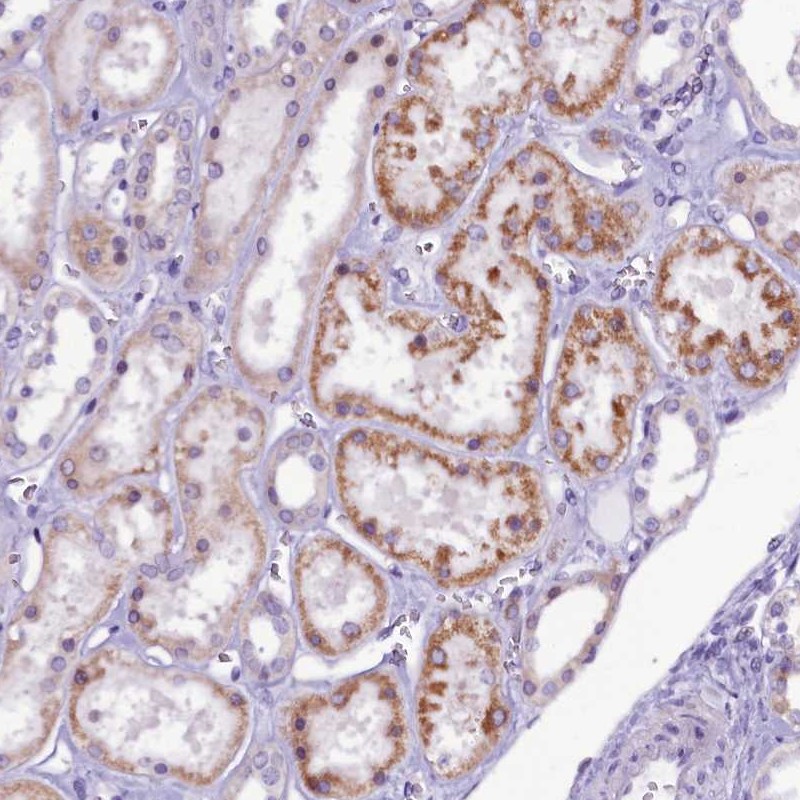

Immunohistochemical staining of human kidney shows moderate positivity in tubules.